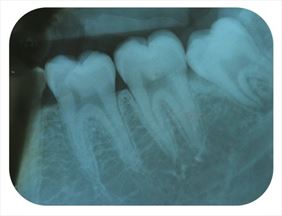

Rentgenodiagnostyka stomatologiczna odgrywa kluczową rolę w precyzyjnej ocenie stanu zdrowia zębów, kości szczęki, żuchwy oraz zatok szczękowych. Dzięki obrazowaniu radiologicznemu możemy wykryć zmiany niewidoczne gołym okiem, takie jak próchnica pod wypełnieniami, ubytki strukturalne, stany zapalne czy torbiele. Zdjęcia rentgenowskie są również niezbędne przy planowaniu leczenia ortodontycznego, implantologicznego oraz chirurgicznego.

W naszym gabinecie wykonujemy różne rodzaje zdjęć RTG, w tym:

• zdjęcia punktowe,